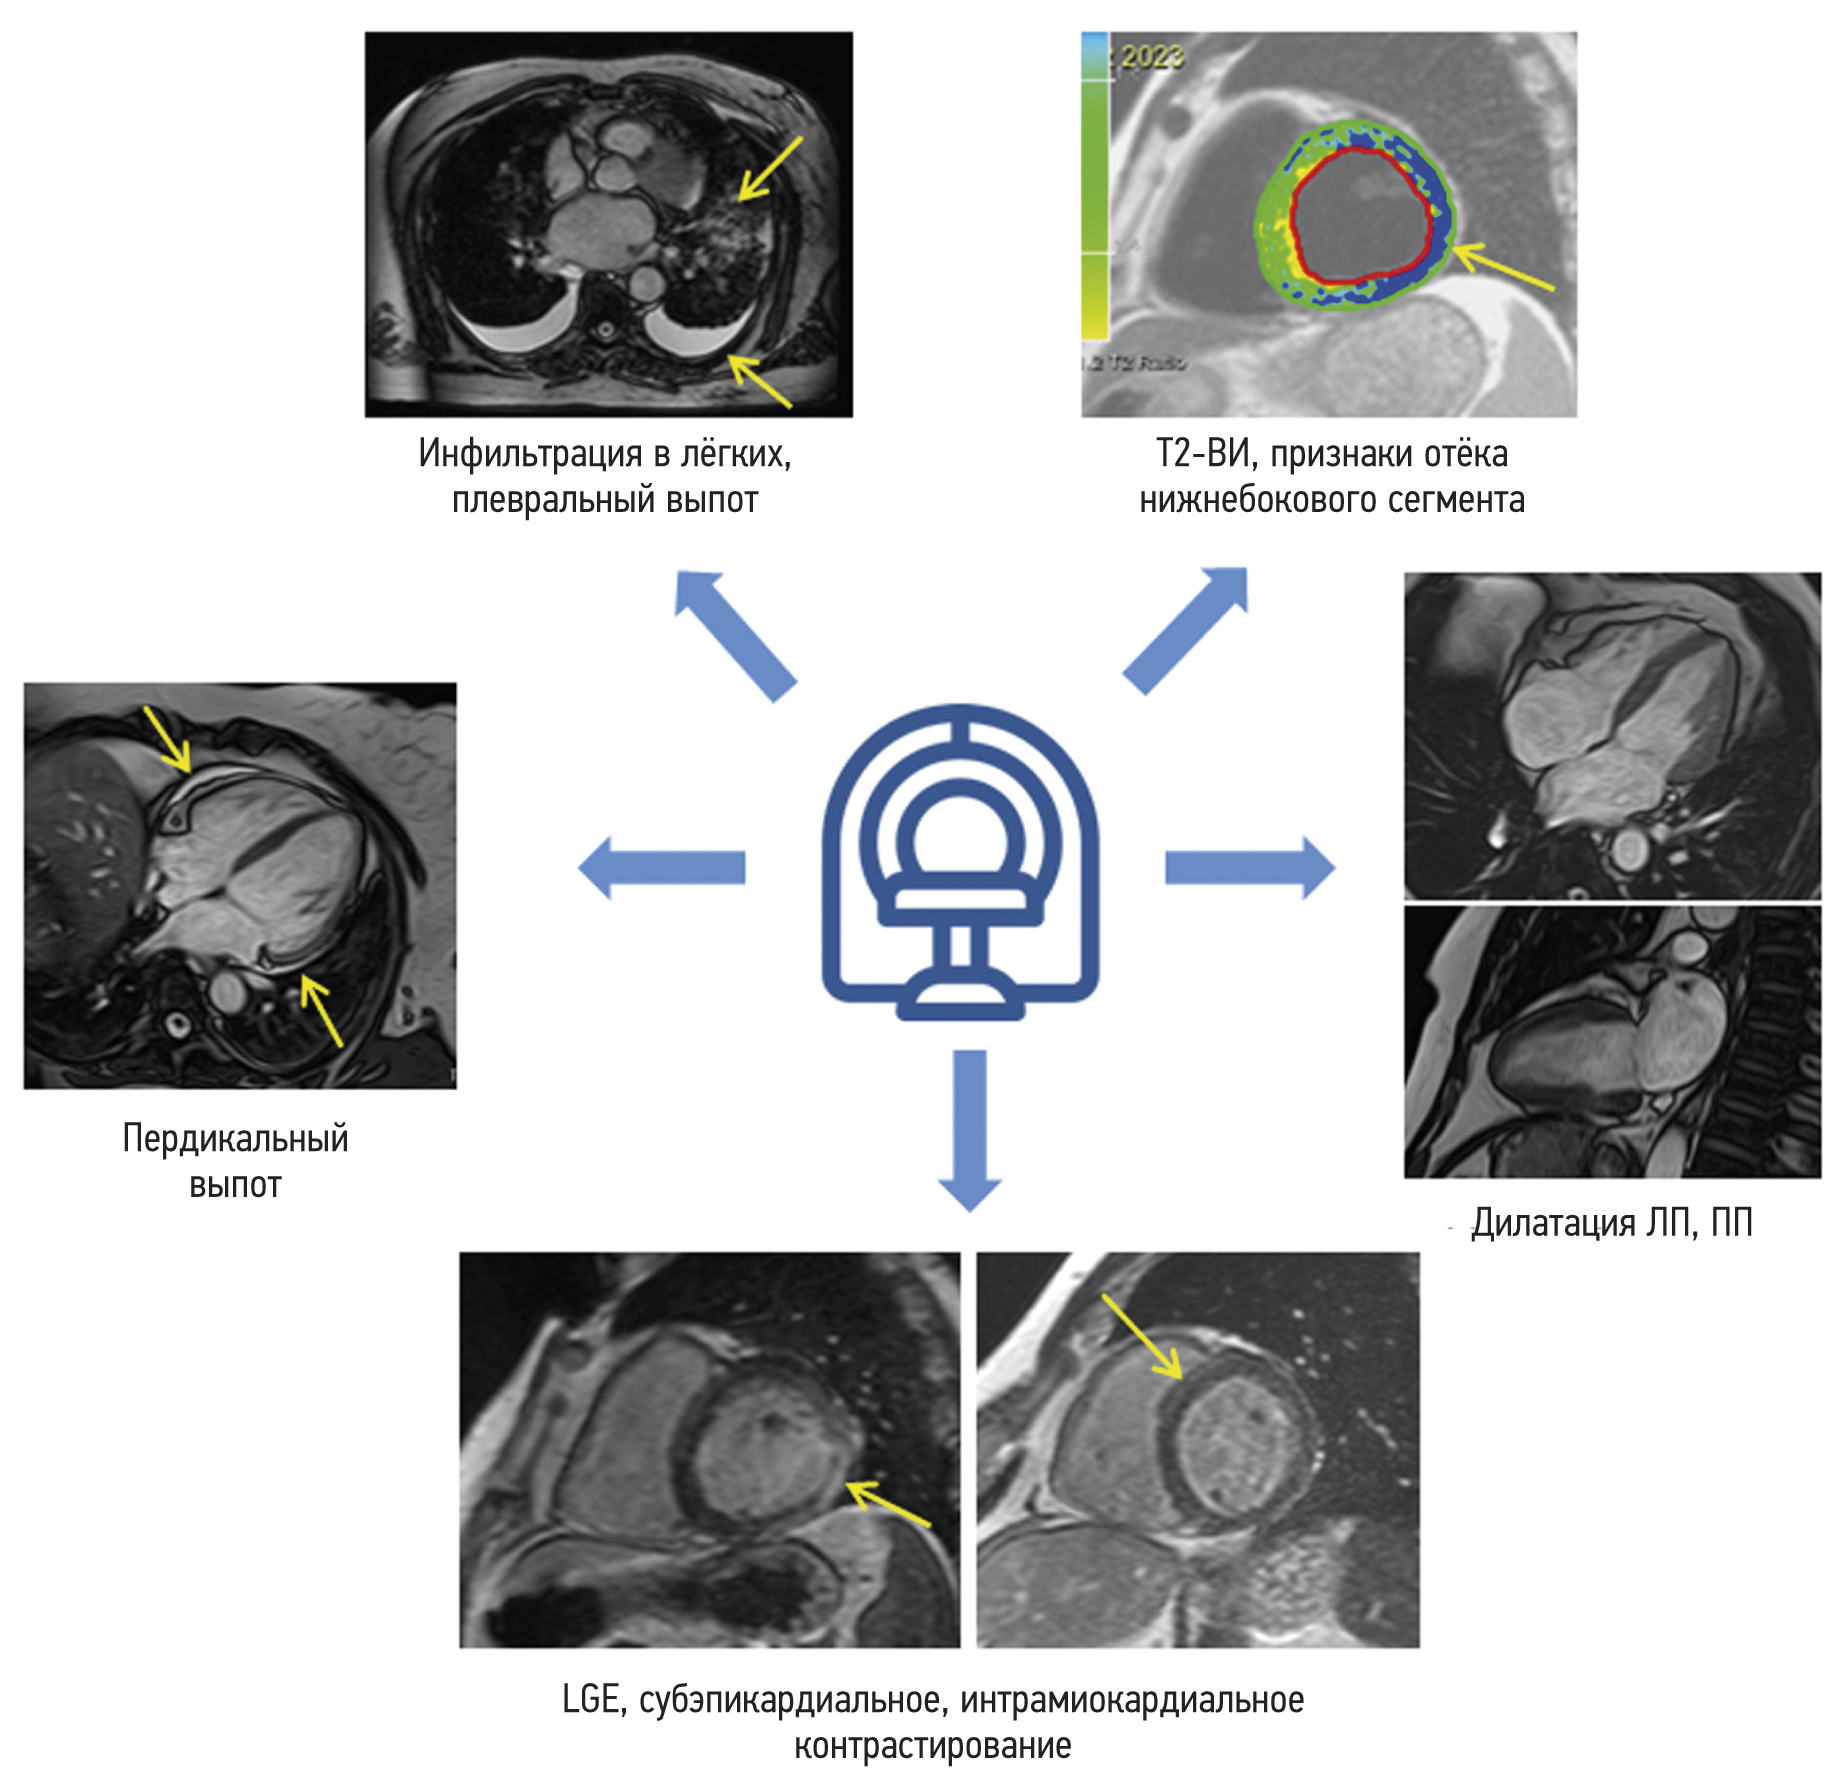

Chronic esophageal fistula as a rare cause of secondary osteomyelitis of the thoracic spine

Infectious diseases affecting the spine are inflammatory destructive diseases that involved the organ and its structural elements as a result of infection by hematogenic, lymphogenic, or contact pathways, including may be a complication of surgical intervention. In arriving at an accurate diagnosis, it is extremely important to evaluate the anamnesis, the clinical picture, as well as the data of laboratory studies and radiation diagnostics in the aggregate.

This article presents a clinical case with the development of secondary ThVII–ThVIII vertebral spondylitis due to esophageal fistula. At the initial diagnosis, spondylitis was associated with spinal anesthesia performed six months prior to onset of the disease, as there was a fistulous defect on the skin in the lumbar region. Consequently, surgical interventions were performed three times in a surgical hospital at the place of residence. The data from the endoscopic examination, as well as the patient’s complaints regarding the relationship between meals, the appearance of pain, and the nature of the discharge from the fistula were not taken into account by doctors initially. With the help of an additional examination, including computed tomography of the esophagus with oral contrast and computed tomography fistulography, the main diagnosis was esophageal fistula. Thoracic spondylitis was only a secondary complication.

Thus, the final diagnosis of back pain and fistula in the lumbar region should be formulated after differential diagnosis with alternative diseases of the spine.